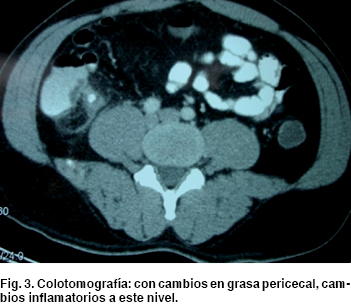

Se propone estudio ultrasonográfico abdominal donde se notan cambios en región pericecal y líquido libre a este nivel (Figura 2). Así como colotomografía denotando cambios en grasa pericecal, cambios inflamatorios a este nivel. Por lo que se decide someterlo a exploración quirúrgica (Figura 3). Se realiza laparotomía exploradora, encontrando líquido libre purulento a nivel de fosa iliaca derecha, y se evidencia a nivel de ciego, remanente apendicular de aproximadamente 1 cm, con cambios isquémicos, y perforación a nivel de la base del ciego. Se realiza hemicolectomía derecha con ileo-transverso anastomosis latero-lateral, y se envía pieza quirúrgica a patología (Figura 4).